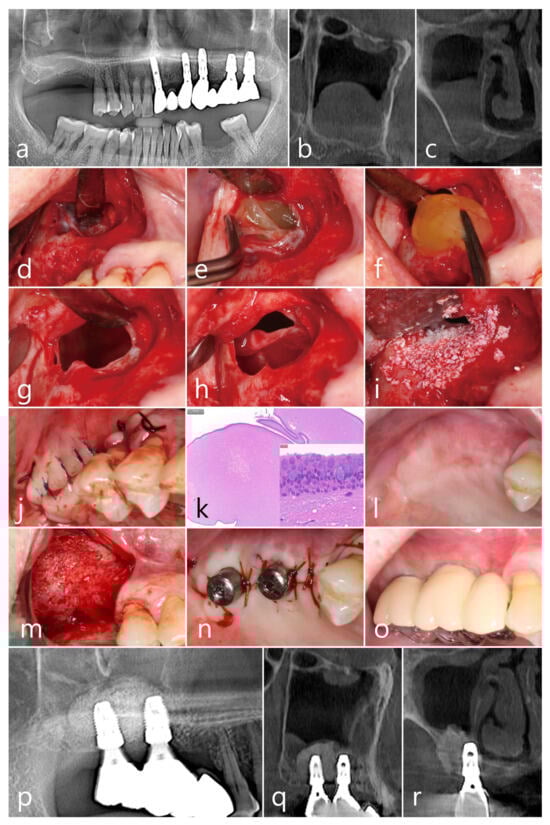

2.3. Case 3